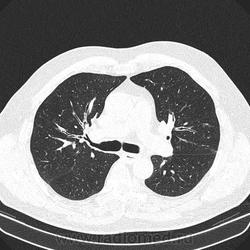

Альвеолярное кровоизлияние.

Полисегментарная пневмония.

оказалось ТЭЛА.

эту пневмонию вылечили, через некоторое время пациент поступил с подобной картиной в другом легком.